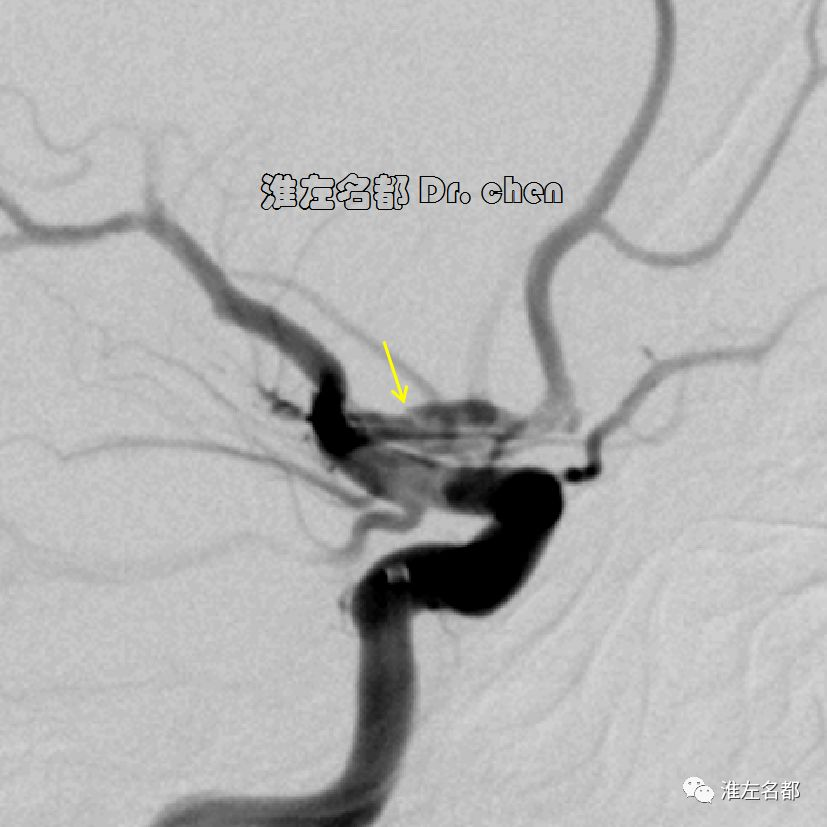

△经.035”泥鳅导丝将中间导管(Navien 058,125cm)送至左侧颈内动脉岩骨段,而后长鞘跟进至左侧颈内动脉,再经泥鳅导丝将中间导管送至海绵窦段,微导管(Rebar 27)在微导丝导引下进入左侧大脑中动脉M2段,造影证实位于真腔后,经微导管释放取栓支架(S AB 6*30mm)后造影:左侧颈内动脉远端充盈缺损,管腔严重狭窄;左侧大脑中动脉近端严重狭窄。

3.脑动脉夹层临床确诊依赖于影像学检测到典型夹层征象:内膜征/双腔征、长段不规则/丝线样狭窄、壁内血肿、夹层动脉瘤等。本患儿DSA显示左侧颈内动脉末端和大脑中动脉主干长段狭窄,且大脑中动脉主干狭窄呈“丝线样”,符合夹层影像学征象。

5.术中,取栓支架仅取出小块血栓,推测取栓支架压迫和中间导管逆向回收支架时按压假腔是夹层真腔得以恢复的主要原因。

6.在夹层真腔得以基本恢复后,DSA于左侧颈内动脉末端、大脑前和中动脉近端均检测到典型“内膜征”,进一步确定了夹层诊断。